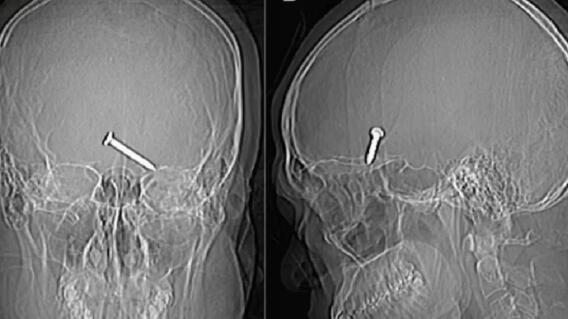

Mientras intentaba arreglar el artefacto, este se disparó y le introdujo una puntilla de tres centímetros muy cerca del ojo.

El sujeto no llevaba gafas de protección y el clavo se insertó en el sector frontal de su cerebro, a tan solo centímetros del globo ocular izquierdo.